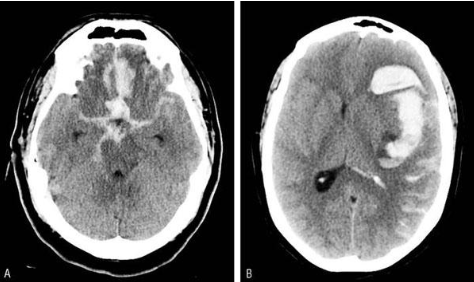

HSA IMAGEN

A

Dx de imágen de HSA

TC

- Temprano puede aparecer normal

AngioTAC

- Buscamos aneurisma SIEMPRE